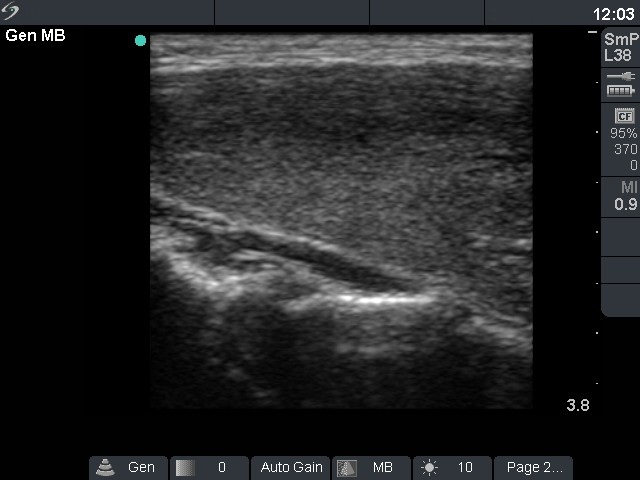

Follow-up investigation 12 months after first visit (ultrasonographic picture 2)

Patient on daily 10 mg methimazole therapy in euthyroid state

Right lobe, longitudinal scan.